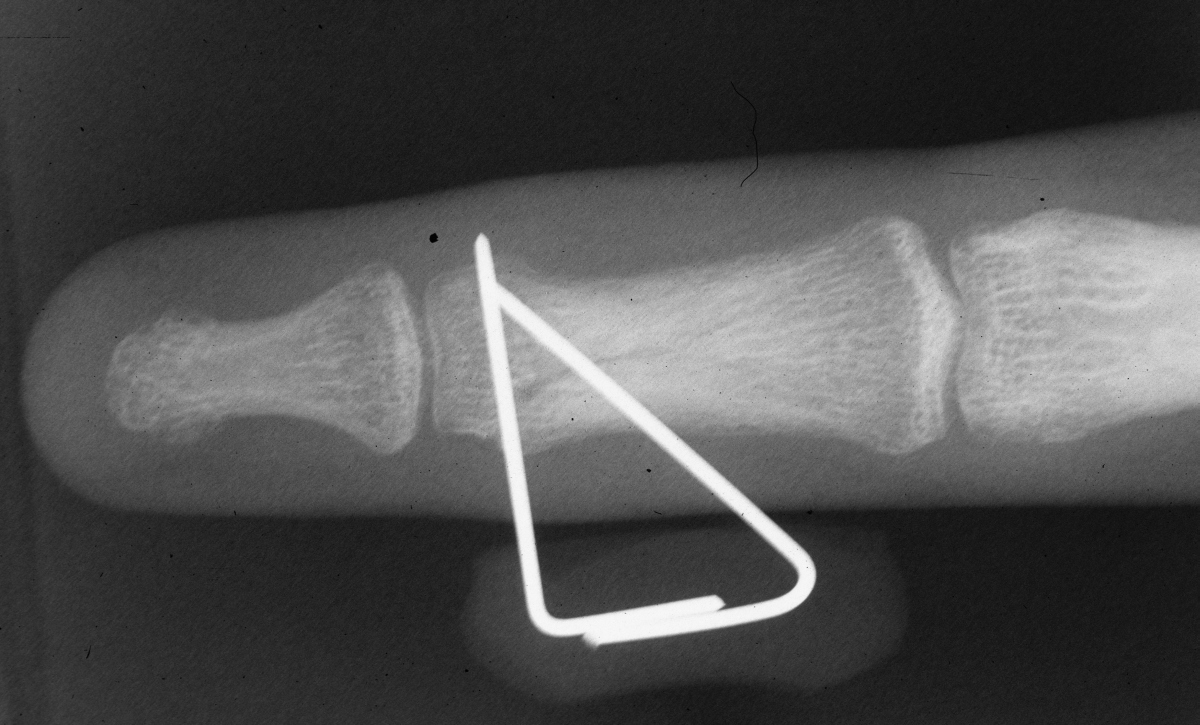

Carol lin, md & brad merk, md. There is at least a theoretically increased risk if reduction is determined to be adequate, then a guide pin may be placed through a percutaneous incision. With special reference to percutaneous knowles. Twenty three patients had other medical conditions. A femoral neck fracture most often results from a recent fall on the affected hip. Garden 1 fractures collapse less frequently than garden 2 fractures, but both have high rates of fracture collapse when treated to union with in situ percutaneous pin fixation. Femoral neck fractures close to the hip joint are easy to recognise. It is a fracture that is commonly found in older individuals who are suffering from osteoporosis and athletes. Displacement of femoral neck fracture will disrupt the blood supply and cause an intracapsular hematoma (effect is controversial). The femoral neck (femur neck or neck of the femur) is a flattened pyramidal process of bone, connecting the femoral head with the femoral shaft, and forming with the latter a wide angle opening medialward. There were 36 garden grade iii and 26 grade iv fractures. Treatment may consist of repair or replacement. Femoral neck fracture is a type of hip fracture common in elderly, osteoporotic women. Carol lin, md & brad merk, md. They generally lead to immediate immobility. The wire is driven into the femoral head. Femoral neck fractures are a subset of proximal femoral fractures.